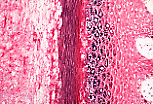

皮肤系统